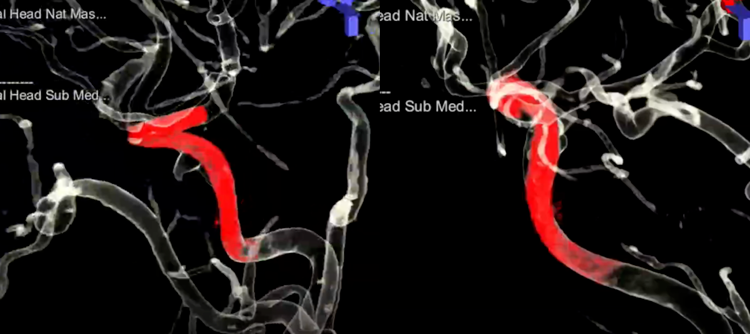

方案确定后,充分双抗,全麻下进行手术,常规长鞘,置入Cat5。手术中间一个小的细节告诉我们这是一个巨大动脉瘤,内部血栓是新鲜的。应用Cat5做路图的时候,能够看到造影剂进入到血栓内部,勾勒出动脉瘤的大小,同时提示血栓是松动的。除了病变段血管,患者其它血管状态还是很不错的。XT-27到位很容易,尝试着不扩张狭窄,直接跟进Cat5,发现中间导管很容易通过病变近端狭窄段,这说明它不是动脉硬化性的坚硬狭窄。因而,立即调整手术策略,取消球囊预扩张,直接通过中间导管。和设想的一样,Cat5轻松到达大脑中动脉。选择了4mm*40mm的支架,送入过程是顺利的,锚定支架远端位置之后,缓慢释放,推的力量下,可以看到支架顺利张开,即使在狭窄的部位也能看到支架完全打开。最终完美释放,即刻造影显示血管完全修复至正常状态,动脉瘤内造影剂进入明显减少。双容积重建显示支架贴壁良好。

双容积重建结果,显示支架和血管壁贴合非常好